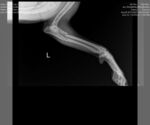

Dog Breed: Boxer (short coat). Adoption Fee: $427.50 includes all applicable MN sales tax. Ricky Bobby has a broken left front leg that will require surgical repair. He will not be available for adoption until after surgery and some recovery time. We are working on getting the surgery scheduled between Aug 25th-Sept 5th. This adorable boy has all of his routine vetting done but still needs to be neutered. He is housebroken and crate trained. Ricky Bobby is wonderful with other dogs and with kids and doesn't seem to bother cats. ***NOT ACCEPTING APPLICATIONS FOR RICKY BOBBY AT THIS TIME*** 9/12 UPDATE: Ricky Bobby had surgery to repair his broken leg yesterday and did amazing!!!